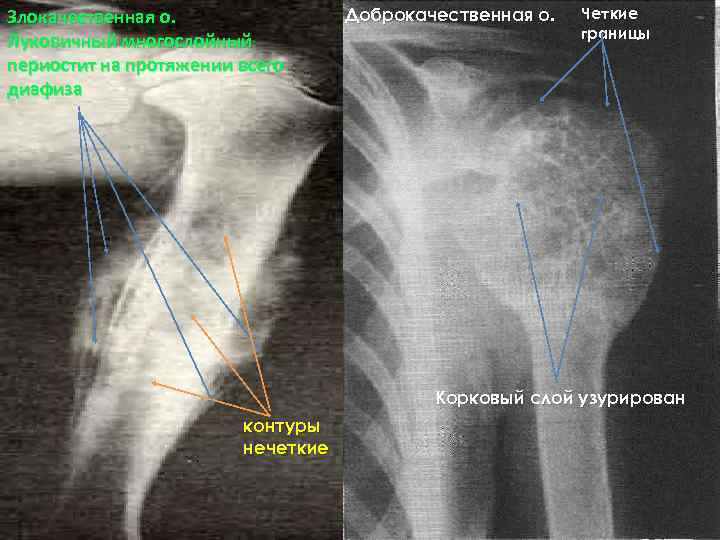

Злокачественная о. Луковичный многослойный периостит на протяжении всего диафиза Доброкачественная о. Четкие границы Корковый слой узурирован контуры нечеткие